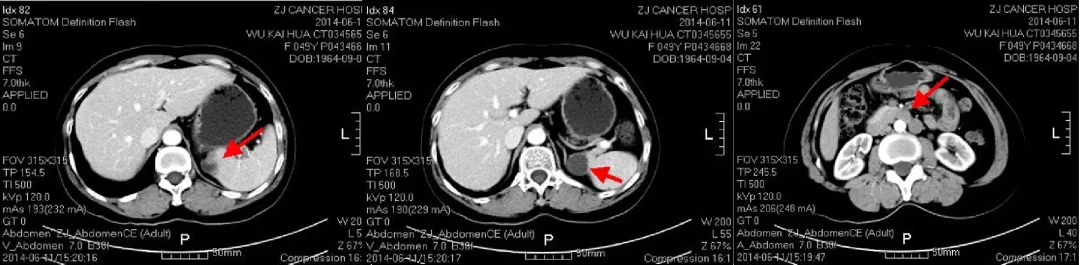

第4次复发(PFI4th=11个月)

2017-10-26当地查CA125水平为46.3U/ml,2017-12-4我院查CA12水平为110.9U/ml,CT显示肝肾间隙及右肝包膜下片状影较前增大,考虑疾病复发。

患者不愿意接受手术,2017.12.15-2018.4.12行多西他赛+卡铂化疗6疗程。

CT检查结果